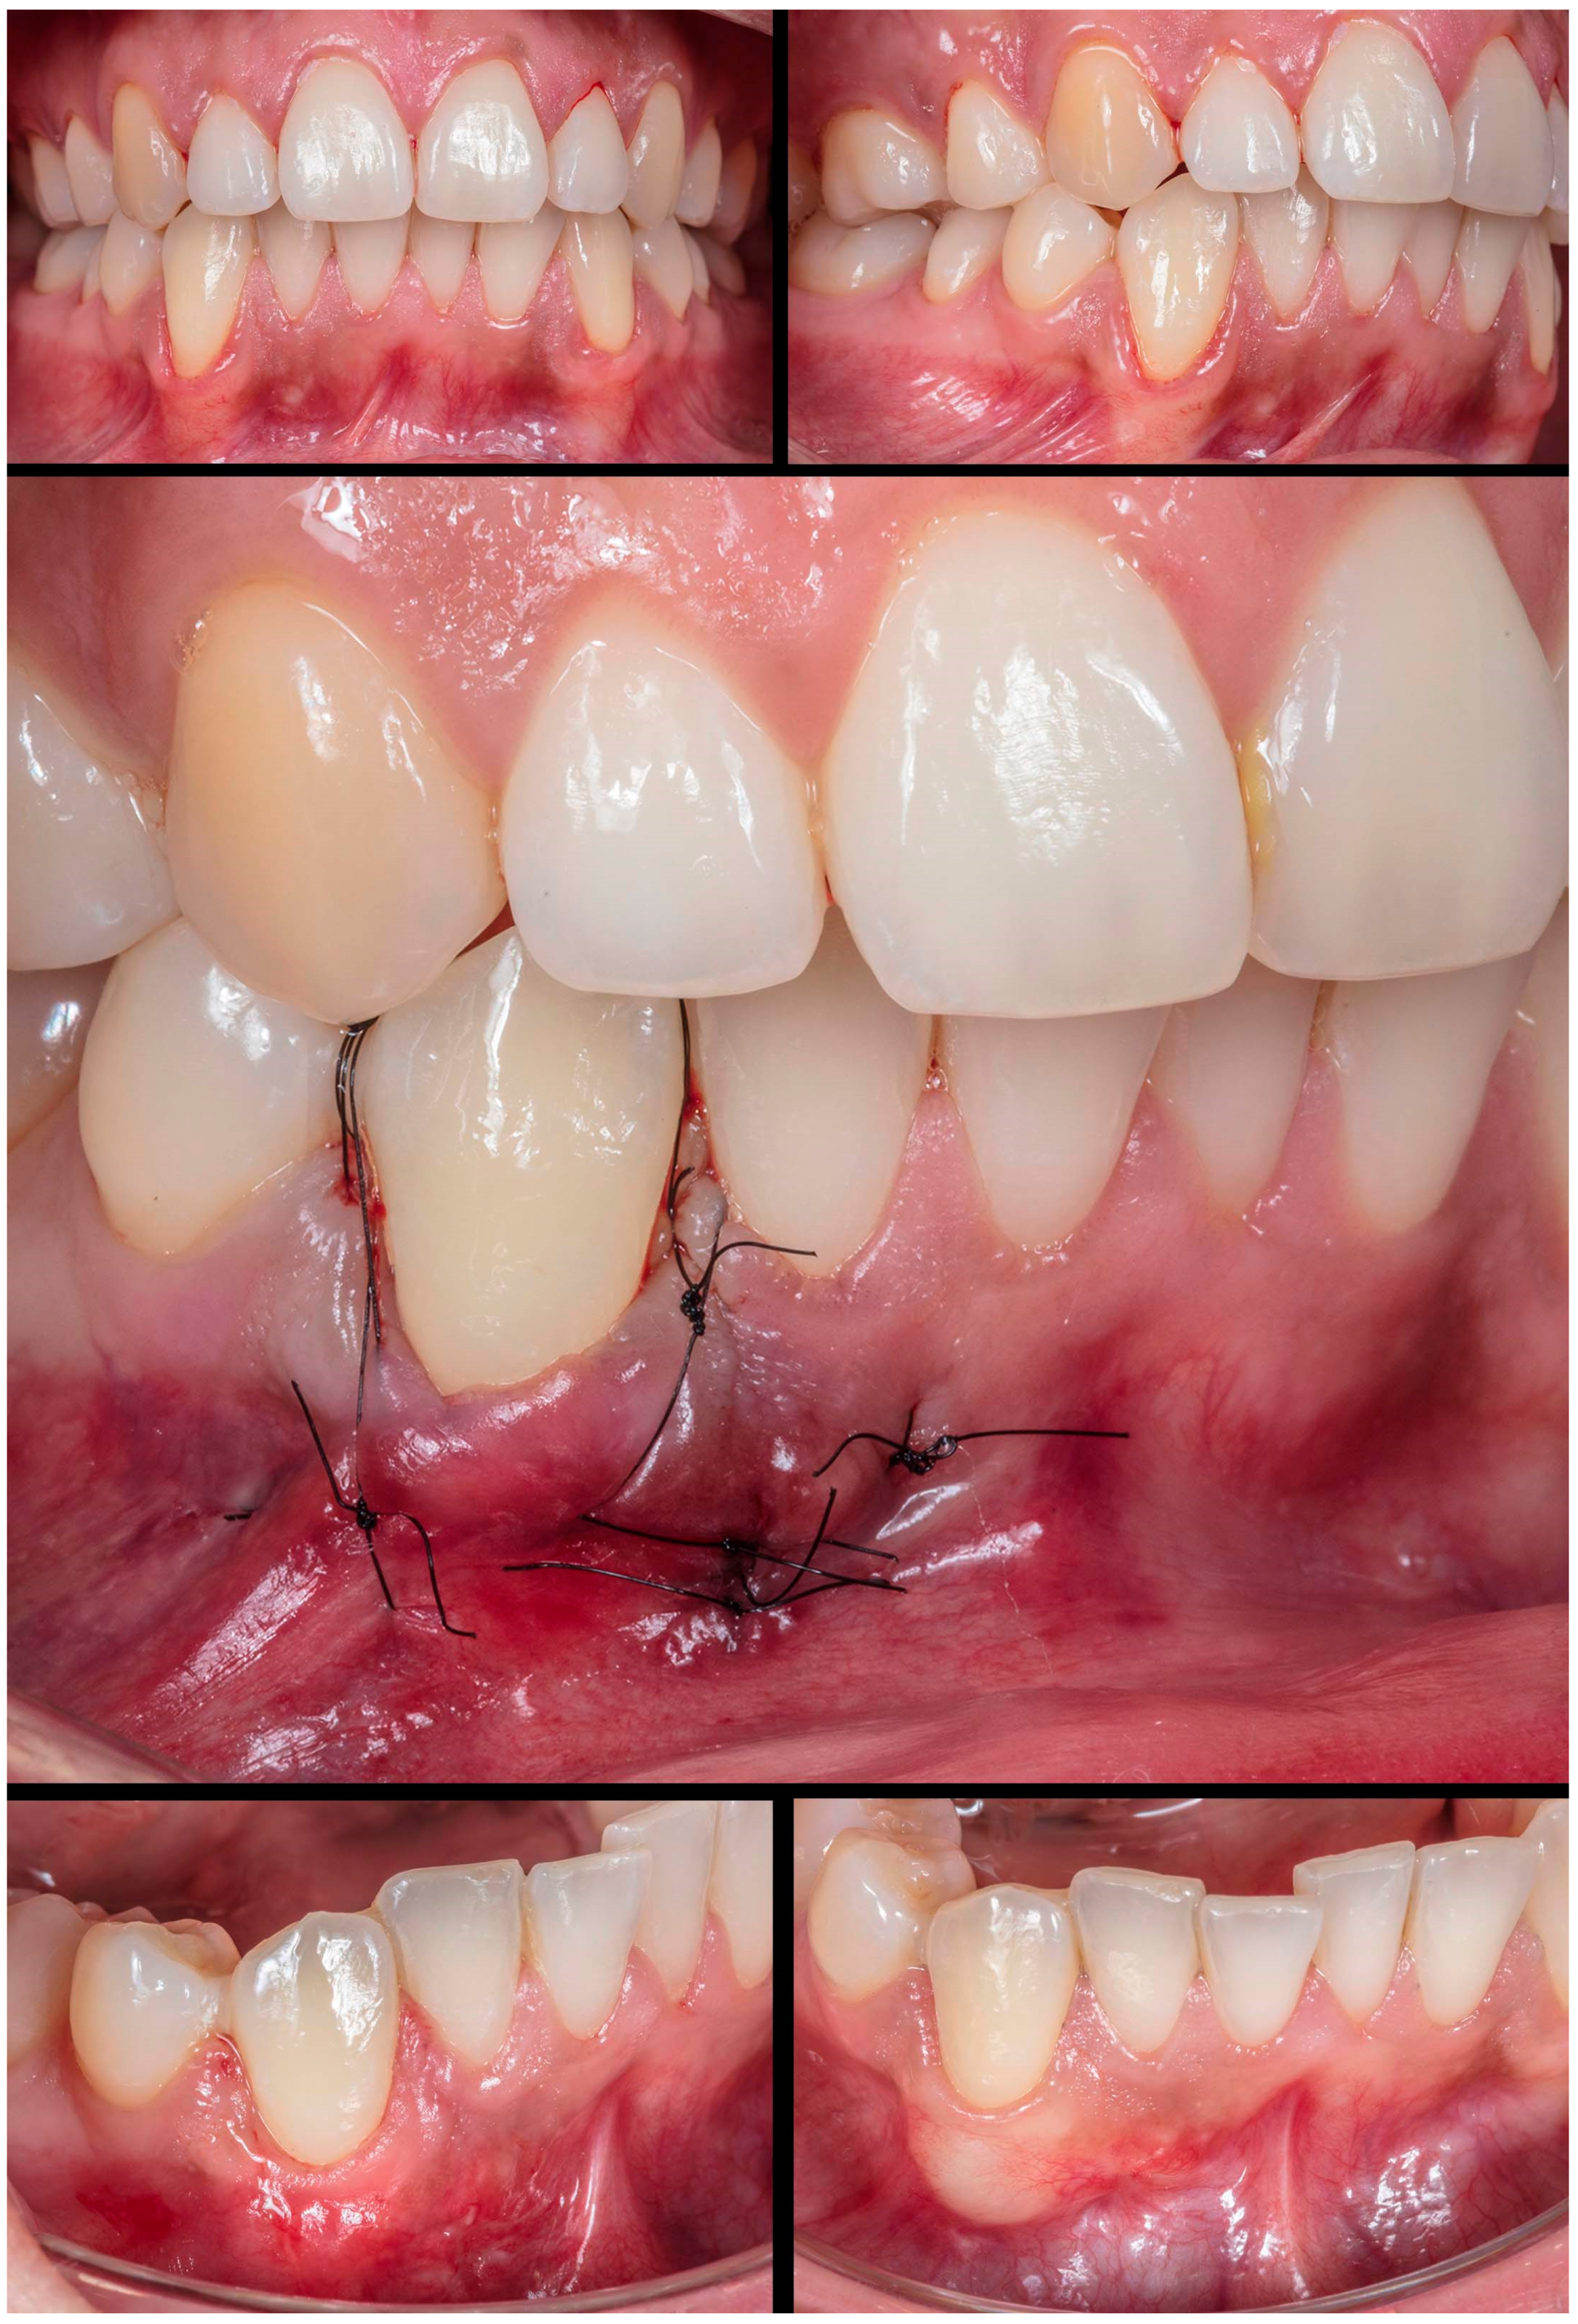

Figure 7.

Case 6 shows initial pictures of the multiple GR defects (#43-#45); a picture showing the final aspect immediately after surgery (double-crossed suture); and the healing period after 1 and 6 months.

Figure 6) was done in a single tooth (#43), which was buccally positioned, classified as RT1, presenting 3mm of GR. Case performed yet in the anterior and buccal region of the mandible with one vertical incision. After MiTT, double-crossed suture was made to position the soft tissue coronally and keep it stable. After 7 days and 1 year, 100% for RC was reached, and a significant tissue volume was found. Another case (Case 6) was also done in that same region but with increased difficulty. Following toward the posterior region in the lower arch, 3 teeth had GR (#43-#45), respectively, with 1mm, 2mm, and 1mm. It was also found rotation in the premolars. MiTT was done with one vertical incision in the mesial site, and after 7, 14 days, and 1 year, there was 100% RC with no adverse event, even considering the mental nerve proximity (

Figure 7).